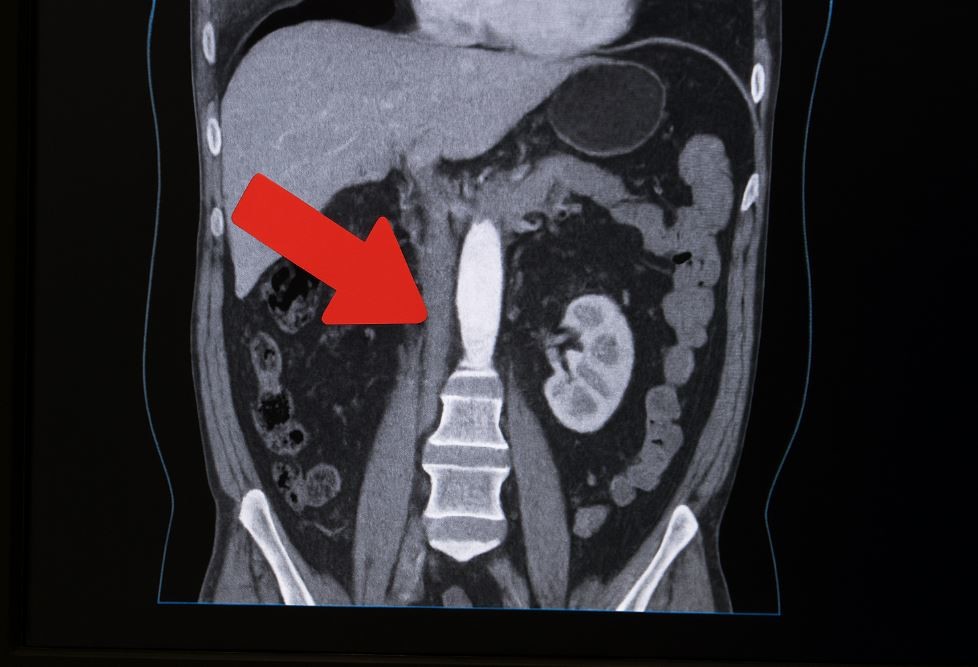

복부 대동맥류는 배 속의 가장 큰 혈관인 대동맥 일부가 약해지면서 풍선처럼 부풀어 오르는 질환이다.

겉으로 보이는 증상이 거의 없어 ‘조용한 시한폭탄’이라 불리지만, 한 번 파열되면 대량 출혈로 이어져 생명을 잃을 수 있다. 최근 10여 년 사이 국내 복부 대동맥류 환자가 급격히 늘었다는 분석 결과가 나오며, 고령화 사회에서 그 위험성이 다시 주목받고 있다.